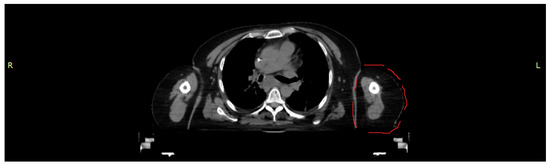

A CT scan of a female torso, acquired on a Brilliance CT Big Bore Oncology scanner (Philips, Hamburg, Germany) operating at 290 mA and 120 kV, was used to obtain the data for both morphology and density values as the basis for an anthropomorphic phantom representing part of the left upper arm (Figure 1). Based on density (CT numbers), the images were segmented in 3D Slicer (Alliance for Medical Image Computing (NA-MIC), Boston, MA, USA) into tissue classes corresponding to skin, cortical bone, bone marrow and soft tissue. The segmented tissues were exported as Standard Transformation Language (STL) files.

Figure 1. CT scan used as template for the partial upper arm phantom (section outlined in red).